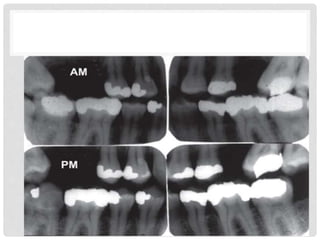

COMPARING POST- AND

ANTEMORTEM DENTAL DATA

• Features compared include tooth morphology and

associated bony structures, pathology and restorations

• An individual with multiple dental treatment and unusual

features has a better likelihood of being identified than

someone with no extraordinary dental characteristics